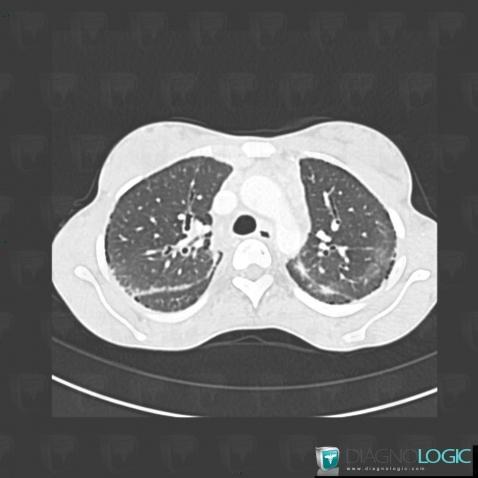

Sarcoïdose, Parenchyme pulmonaire, Scanner

Voici les informations spécifiques à l'image clé ci dessus:

- Diagnostic Sarcoïdose, Localisation(s) Parenchyme pulmonaire, comportant les gammes Maladie prédominant dans les régions supérieures du poumon, Micronodules périlymphatiques pulmonaires, Maladie prédominant en périphérie ou en sous pleural